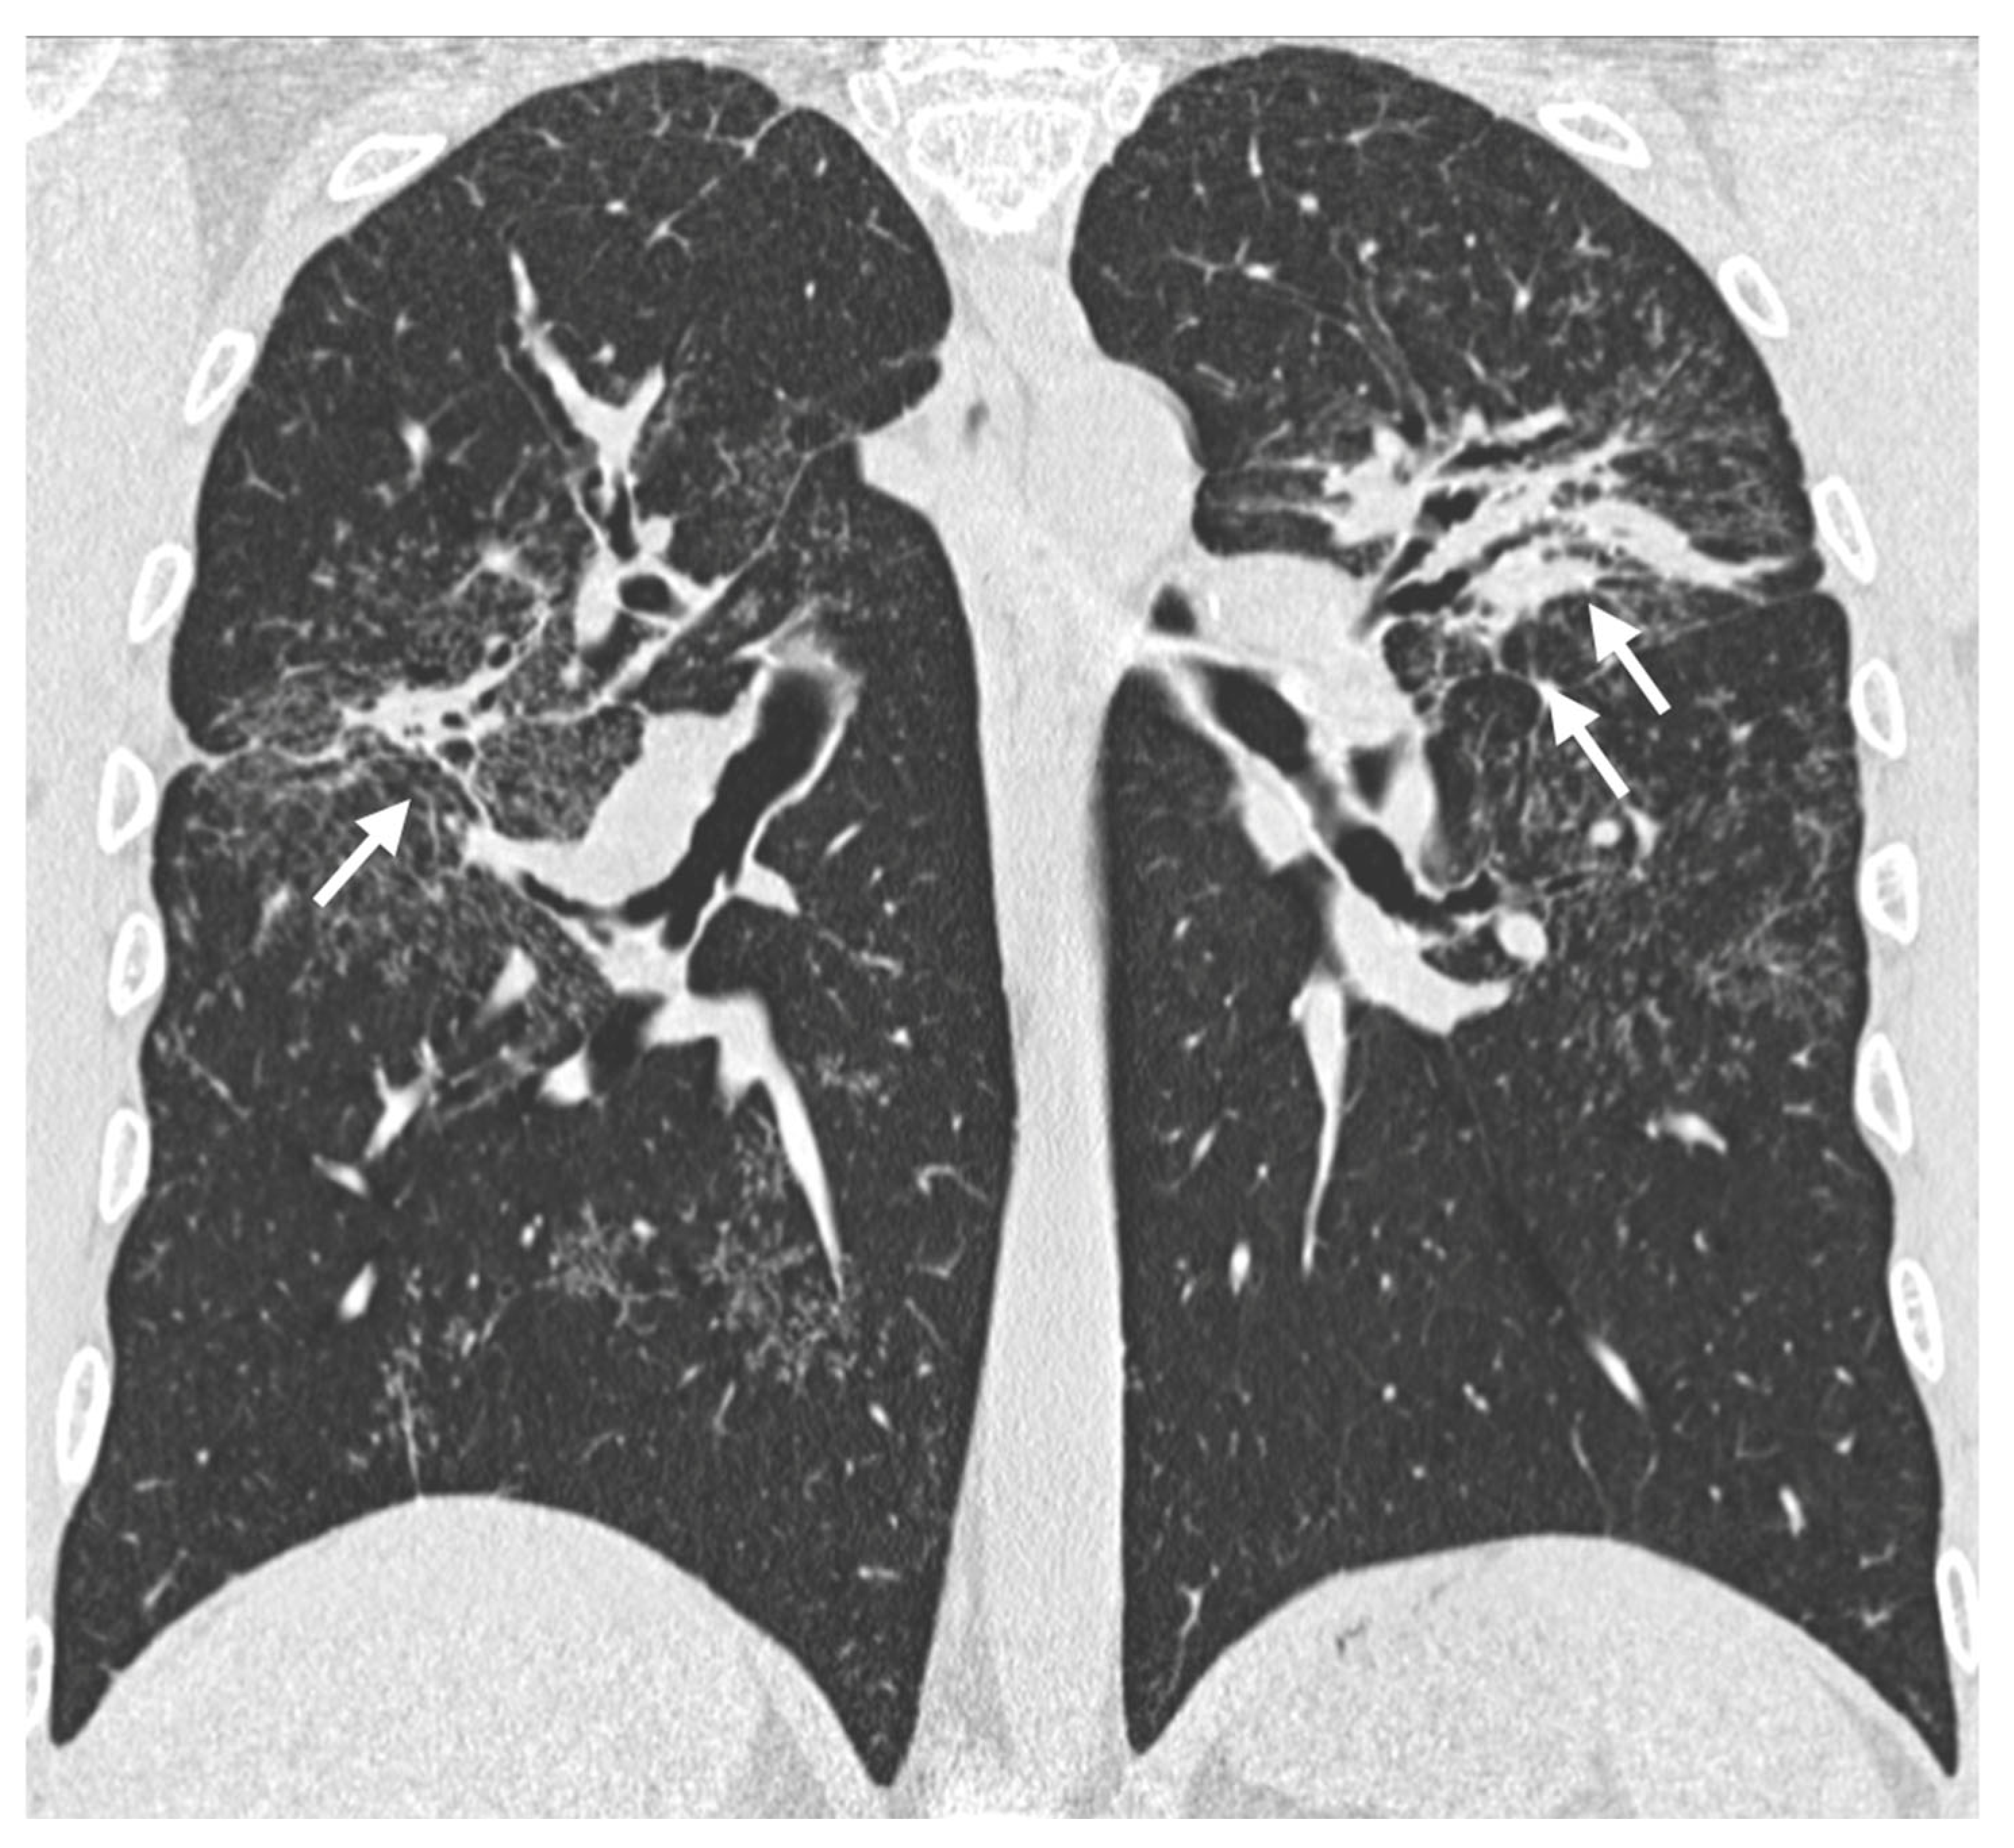

4. Pulmonary Interstitium

4.1. Typical Imaging

4.2. Atypical Imaging

5. Fibrosis

5.1. Progressive Fibrosing Form

| Distribution | Perilympathic (75–90% of cases); bilateral and symmetric involvement, especially in the middle and upper lobes |

| Nodule size | Micronodules 2–4 mm in diameter |

| Morphology | Nodules with well-defined margins, round shape |

| HRCT localization | Peribronchovascular interstitium, interlobar fissures, interlobular septa |

| Evolution | Possible coalescence of micronodules into macronodules over time |

| Characteristic | Description |

|---|---|

| Incidence | Approximately 20% of patients with sarcoidosis |

| Origin | Chronic inflammation, long-lasting disease, or phenotypic susceptibility |

| Alterations | Linear opacities, traction bronchiectasis, architectural distortion |

| Distribution | Predominantly in the upper lobes and peribronchovascular regions |

| Honeycombing | Present in about 10% of patients, typically localized in middle-upper lobes |